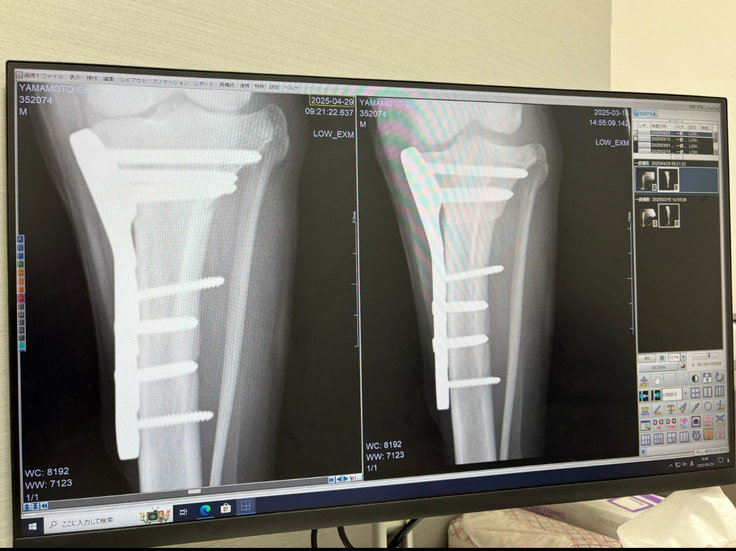

左が最新、右が1か月前

骨を切った後がより見えにくくなってきていました。